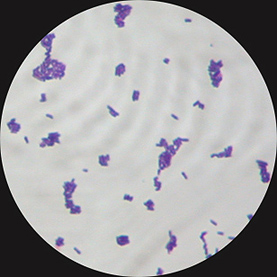

- Voici l'aspect de la coloration de Gram réalisée sur ces colonies (G X 1000) :